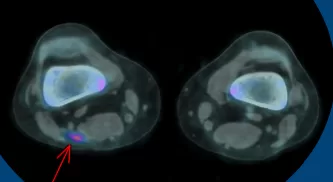

PET-CT DE CORPO INTEIRO (11/04)

ANÁLISE COMPARATIVA PET-CT DE CORPO INTEIRO PÓS-TRATAMENTO

Pré

Pós

- A IMPORTÂNCIA DO PET-CT NESTE CONTEXTO, JÁ QUE A LESĀO PRIMÁRIA NÃO TERIA SIDO VISTA POR COMPLETO E NEM AS SECUNDÁRIAS.